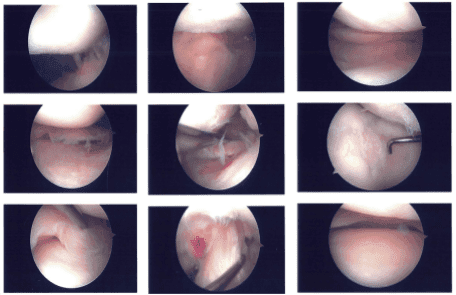

Examination of the patellofemoral joint was again done which showed grade 4 lesion of the trochlea. Abrasion chondroplasty with excision of the frayed margins of the cartilage and balancing margins were performed with the use of shaver. The final picture was taken and saved.

Intraoperative images

We went over the arthroscopic pictures and removed the stitches during the visit. We will continue with ice and elevation of the knee to decrease swelling and pain. We will continue to utilize early mobilization and mechanical prophylaxis to reduce the chances of a deep vein thrombosis.